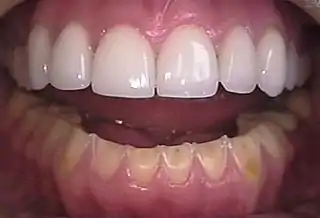

![]() Erosión en los dientes inferiores causada por bulimia. A modo de comparación, los dientes superiores se restauraron con carillas de cerámica. | ||

Algunos ejemplos de estas conductas no saludables son vomitar, abusar de laxantes y diuréticos, usar saunas o baños calientes para perder líquido corporal, hacer ejercicio excesivo, fumar para saciar el apetito, restringir o evitar alimentos, tomar pastillas para adelgazar y restringir el consumo de líquidos. Estos trastornos alimentarios y otras conductas para perder peso pueden causar problemas de salud a corto o largo plazo tales como erosión dental, deficiencias nutricionales, irregularidades menstruales, baja densidad ósea, deshidratación y estrés por calor. Se han reportado arritmias cardiacas en personas con anorexia nerviosa y bulimia nerviosa. Los trastornos renales, como cálculos renales e insuficiencia renal, también se han reportado en estas poblaciones.

- Aumento en la frecuencia de caries dentales.

- Alteración o pérdida esmalte dental.